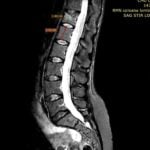

Infiltrațiile transforaminale sunt proceduri medicale minim invazive utilizate pentru diagnosticarea și tratamentul durerilor de spate și a altor afecțiuni legate de coloana vertebrală.

Aceste proceduri implică administrarea de medicamente, cum ar fi corticosteroizii și anestezicele, direct în spațiul în care se află nervii spinali, cunoscut sub numele de foramina.

- Evaluarea inițială: Înainte de a decide să efectuați infiltrații transforaminale, medicul va efectua o evaluare detaliată a stării dumneavoastră de sănătate și va discuta cu dumneavoastră despre simptomele și istoricul durerii.